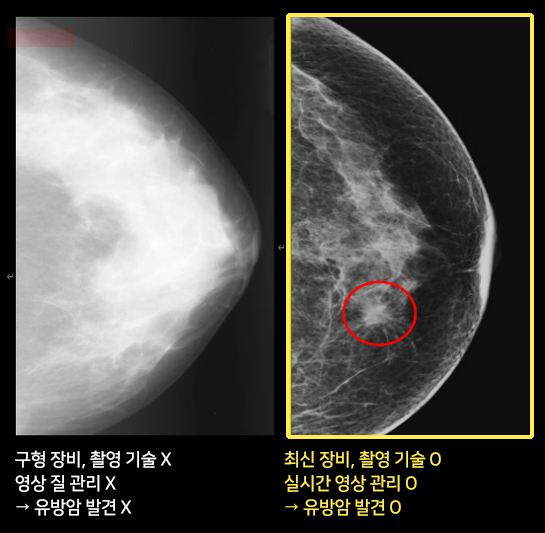

유방촬영술, 다 같은 것이 아닙니다.

√ 유방 전공 영상의학과 전문의의 실시간 판독이 가능한지,

√ 최신 장비, 방사선사의 촬영기술과 관리 능력,

유방 영상의 실시간 질 관리가 가능한지.

이 2가지를 중요하게 보셔야 합니다.

유방촬영술은 유방촬영장비, 촬영하는 방사선사에 따라 영상의 질이 매우 차이납니다. 유사랑영상의학과에서는 유방영상 전문의의 실시간 피드백을 통해 최고 영상의 질을 유지합니다.